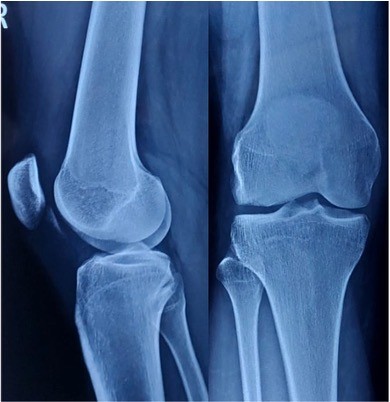

A 20-year-old male (dimensions) presented to our emergency department following a direct injury to his right knee, which occurred while playing basketball. He complained of a click in his right knee joint while playing the sport, which was associated with a suspected lateral patella dislocation that spontaneously relocated. This was associated with severe pain and swelling of the right knee joint. The patient was unable to bear weight following the injury and was brought to our emergency department immediately afterwards. On examination in the emergency department, the patellar appeared relocated, and he had some amount of lateral laxity and apprehension, but it was difficult to assess the laxity due to the swelling of the right knee joint. The patient had tenderness on the lateral aspect of the knee along with inability to move the knee through the range of motion (ROM) more than 0–40° of ROM due to pain and swelling. He was comfortable at 20° of flexion of the knee joint. The patient reported no previous episode of patella dislocation, but did report some injury to the same knee 5 years ago; but he did not have any details of the incident. On examination for generalized laxity, his Beighton Score was 6/9, which corresponds to excessively hypermobile. Fig. 1

Figure 1: Radiographs on presentation of the patient to our emergency room – right knee anteroposterior and lateral view.

The patient was administered painkillers and ice fomentation and underwent an X-ray of his knee joint. An osteochondral fragment was visible in the knee joint, but we were not able to determine where the origin of the fragment was. A computed tomography scan of the knee joint was performed, and the fragment was identified to be originating from the distal LFC and was measuring 2.5 cm × 2.5 cm. The Insall Salvati ratio was 1.36, and the Caton Deschamps Ratio was 1.6. The Tibial Tuberosity–Trocheal Groove (TT–TG) distance was 20 mm, and his knee was a Dejour type B. A standing scannogram was not possible for the patient due to pain. The decision to avoid a tuberosity osteotomy was made as the TT-TG distance was just at the borderline with a slightly high Caton–Deschamps index. The decision to perform a lateral parapatellar arthrotomy with a strong medial patellofemoral ligament (MPFL) reconstruction was deemed sufficient to maintain patella stability. The final decision would be taken intraoperatively after tightening of the MPFL graft regarding the requirement of a tuberosity osteotomy. Fig. 2, 3.